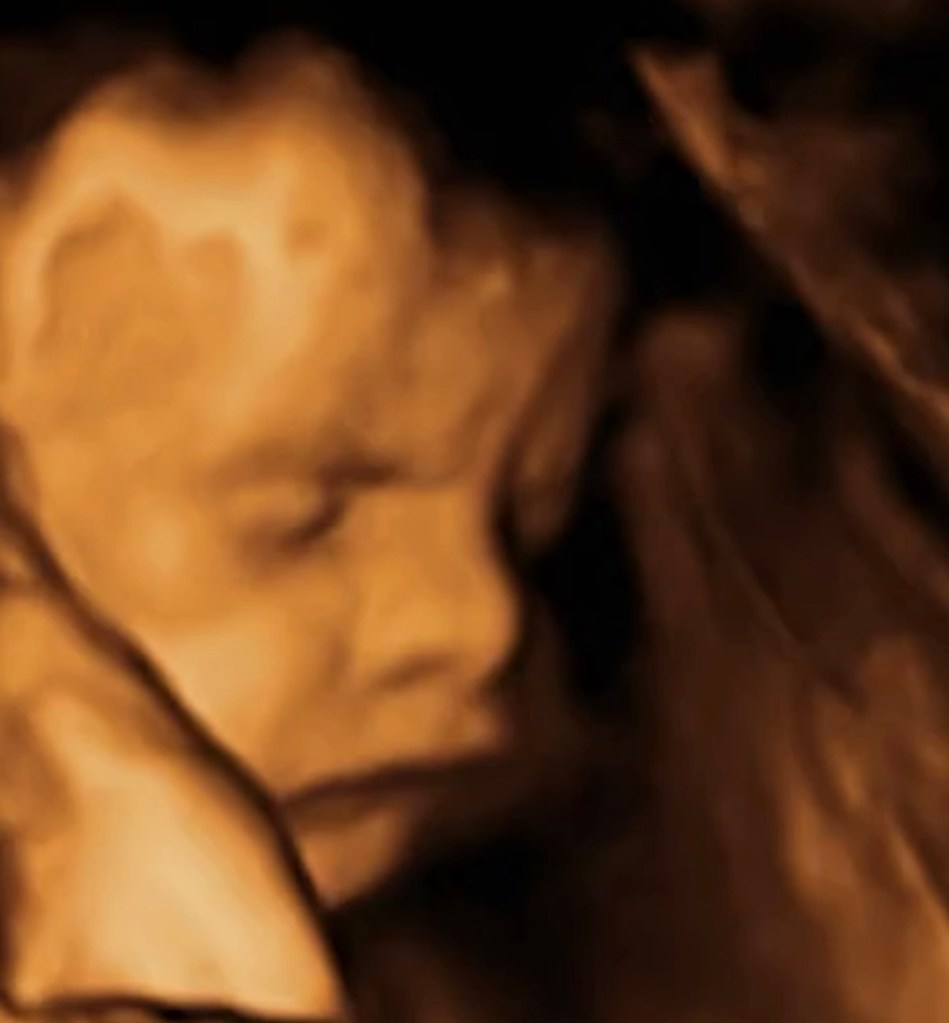

Can you guess what you’re looking at?

It might not be much to us. A hazy reddish glow. Diffuse light. Shadows without edges.

But if you are around 32 weeks pregnant, that glow might be your baby’s view of the world.

Let’s be realistic. This is not high definition vision. Baby is not reading the news inside your belly.

Fetal vision is blurry and diffuse, and it’s likely dominated by red wavelengths, which pass more easily through tissue. And studies of newborn eyes reveal that, even if the picture was perfect, baby wouldn’t be able to make it out anyway.